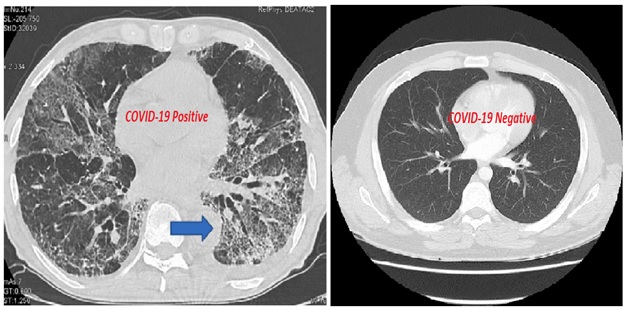

As the accuracy of any machine learning algorithm depends on the type and quality of data that is provided to it, the database for our experiment was very carefully selected. Only those patients(images) were selected whose lung CT scan images showed typical patches on the outer edges of the lungs. first the CT scan images of positive covid and normal healthy person are taken and stored in the computer. Then we are doing some pre-processing steps to enhance the image. We are making separate folders for positive cases and normal cases. For feature extraction and learning of the system, we are using custom vision software based on deep learning algorithm of Microsoft azure. Once the system gets trained, we test the system on the unseen images of positive and normal cases. After getting the results of testing, we check it with the actual condition (positive/normal) of the patient for getting accuracy of the trained model. Next step is to deploy the model,